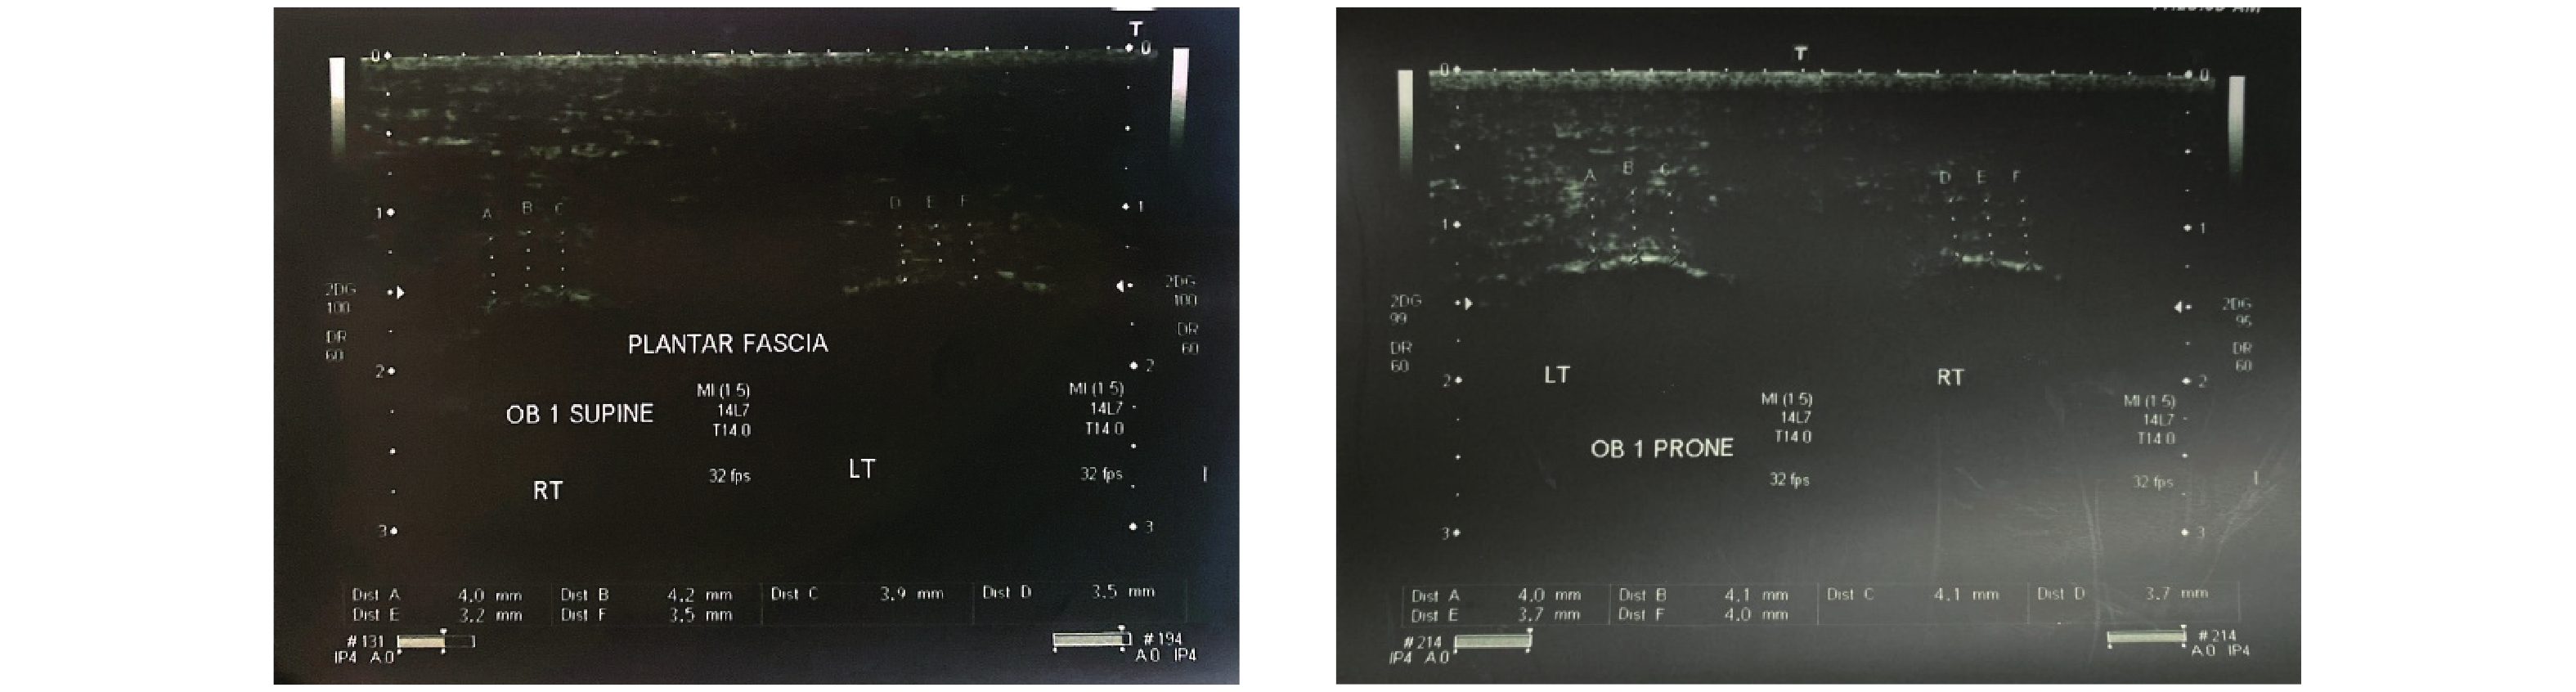

Ahn JH, Lee CW, Park C, Kim YC. Ultrasonographic examination of plantar fasciitis: a comparison of patient positions during examination. J Foot Ankle Res 2016; 9: 38.